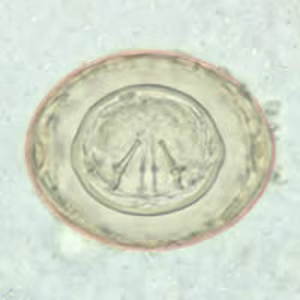

Hymenolepis nana egg in wet mounts.

Hymenolepis nana eggs, zinc PVA trichrome stain.